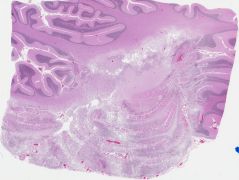

Autopsy showed arterial and venous thromboembolism.  The brain weighted 1155 grams, had a right occipital infarct and a soft left lateral cerebellum, which showed liquefactive necrosis, dystrophic calcification, and well-defined round fungus-like bodies.  The bodies are Michaelis-Gutman bodies.

Malakoplakia usually occurs in the urinary tract.  The Michaelis-Gutman bodies are both extra- and intra-cellular and represent incompletely digested bacteria.  The lysosomes cannot completely digest the bacteria, and the residua produce a target-like appearance on light microscopy.  On electron microscopy, hydroxyapatite crystals are seen which contain calcium, phosphate, iron and carbohydrate and have the appearance of thin needle-like structures as shown by Dr. Rhodes, whose ultramicrographs also showed possible bacteria.  The above minerals and carbohydrate are deposited upon incompletely digested bacteria leading to the appearance of Michaelis-Gutman bodies.  Malakoplakia of the CNS has been reported in both children and adults.  Three previous cases of renal failure all had lesions in the cerebrum, not the cerebellum as in the current case.  In AIDS, malakoplakia lesions show intracellular coccobacilli.

Slide Image:

view high resolution slide image